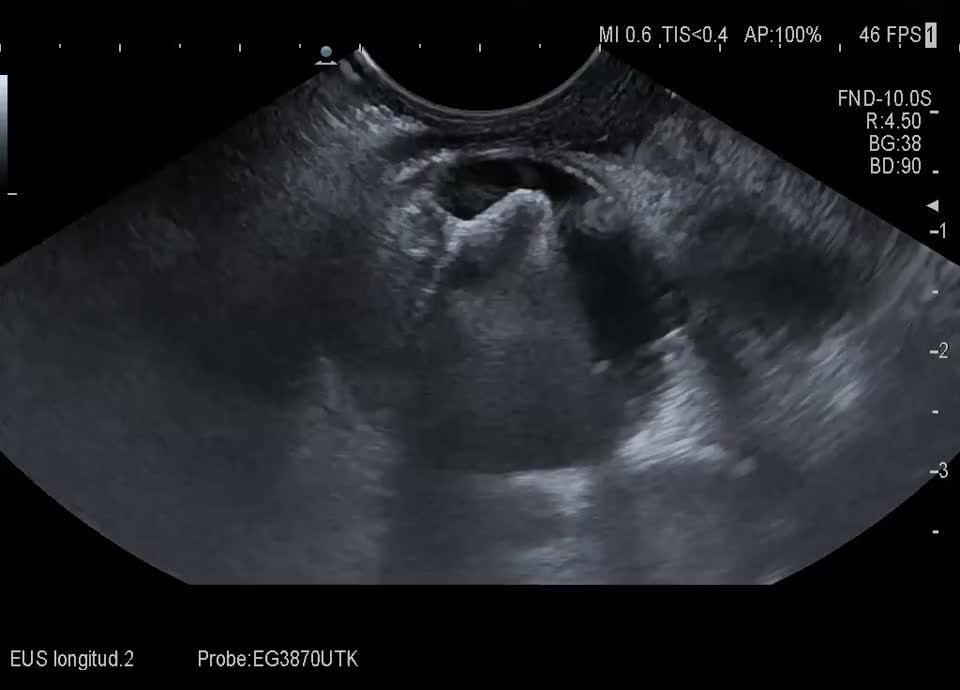

• Endosonographie